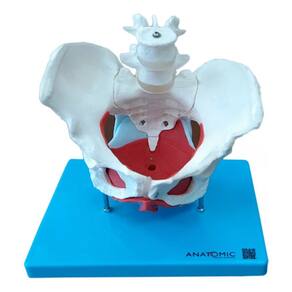

Anatomia Esqueleto Pélvico Pelve Útero 7 Partes Tamanho Natu

Esqueleto Pélvico Feminino, Anatomia Pelve Feminina

Esqueleto Pélvico Feminino, Anatomia Pelve Feminina